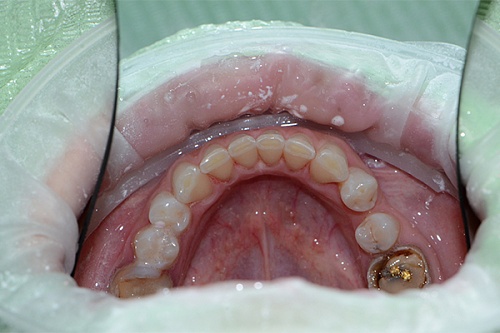

Изменения тканей, которые окружают корни зубов, к сожалению, неизбежны и с возрастом наблюдаются у всех, однако в разном объеме. Так, на развитие пародонтита влияет болезнетворная микрофлора полости рта, которая есть у каждого из нас, но на мы в силах повлиять на ее количество.

Сохранить зубы и пародонт помогает правильная гигиена полости рта дома и в кресле стоматолога, а также своевременное протезирование и имплантация, которые замещают удаленные зубы и равномерно распределяют жевательную нагрузку, не позволяя костной ткани атрофироваться.

Таким образом, по мнению стоматологов, риск возникновения болезней десен на 80% зависит от сознательности самого пациента.